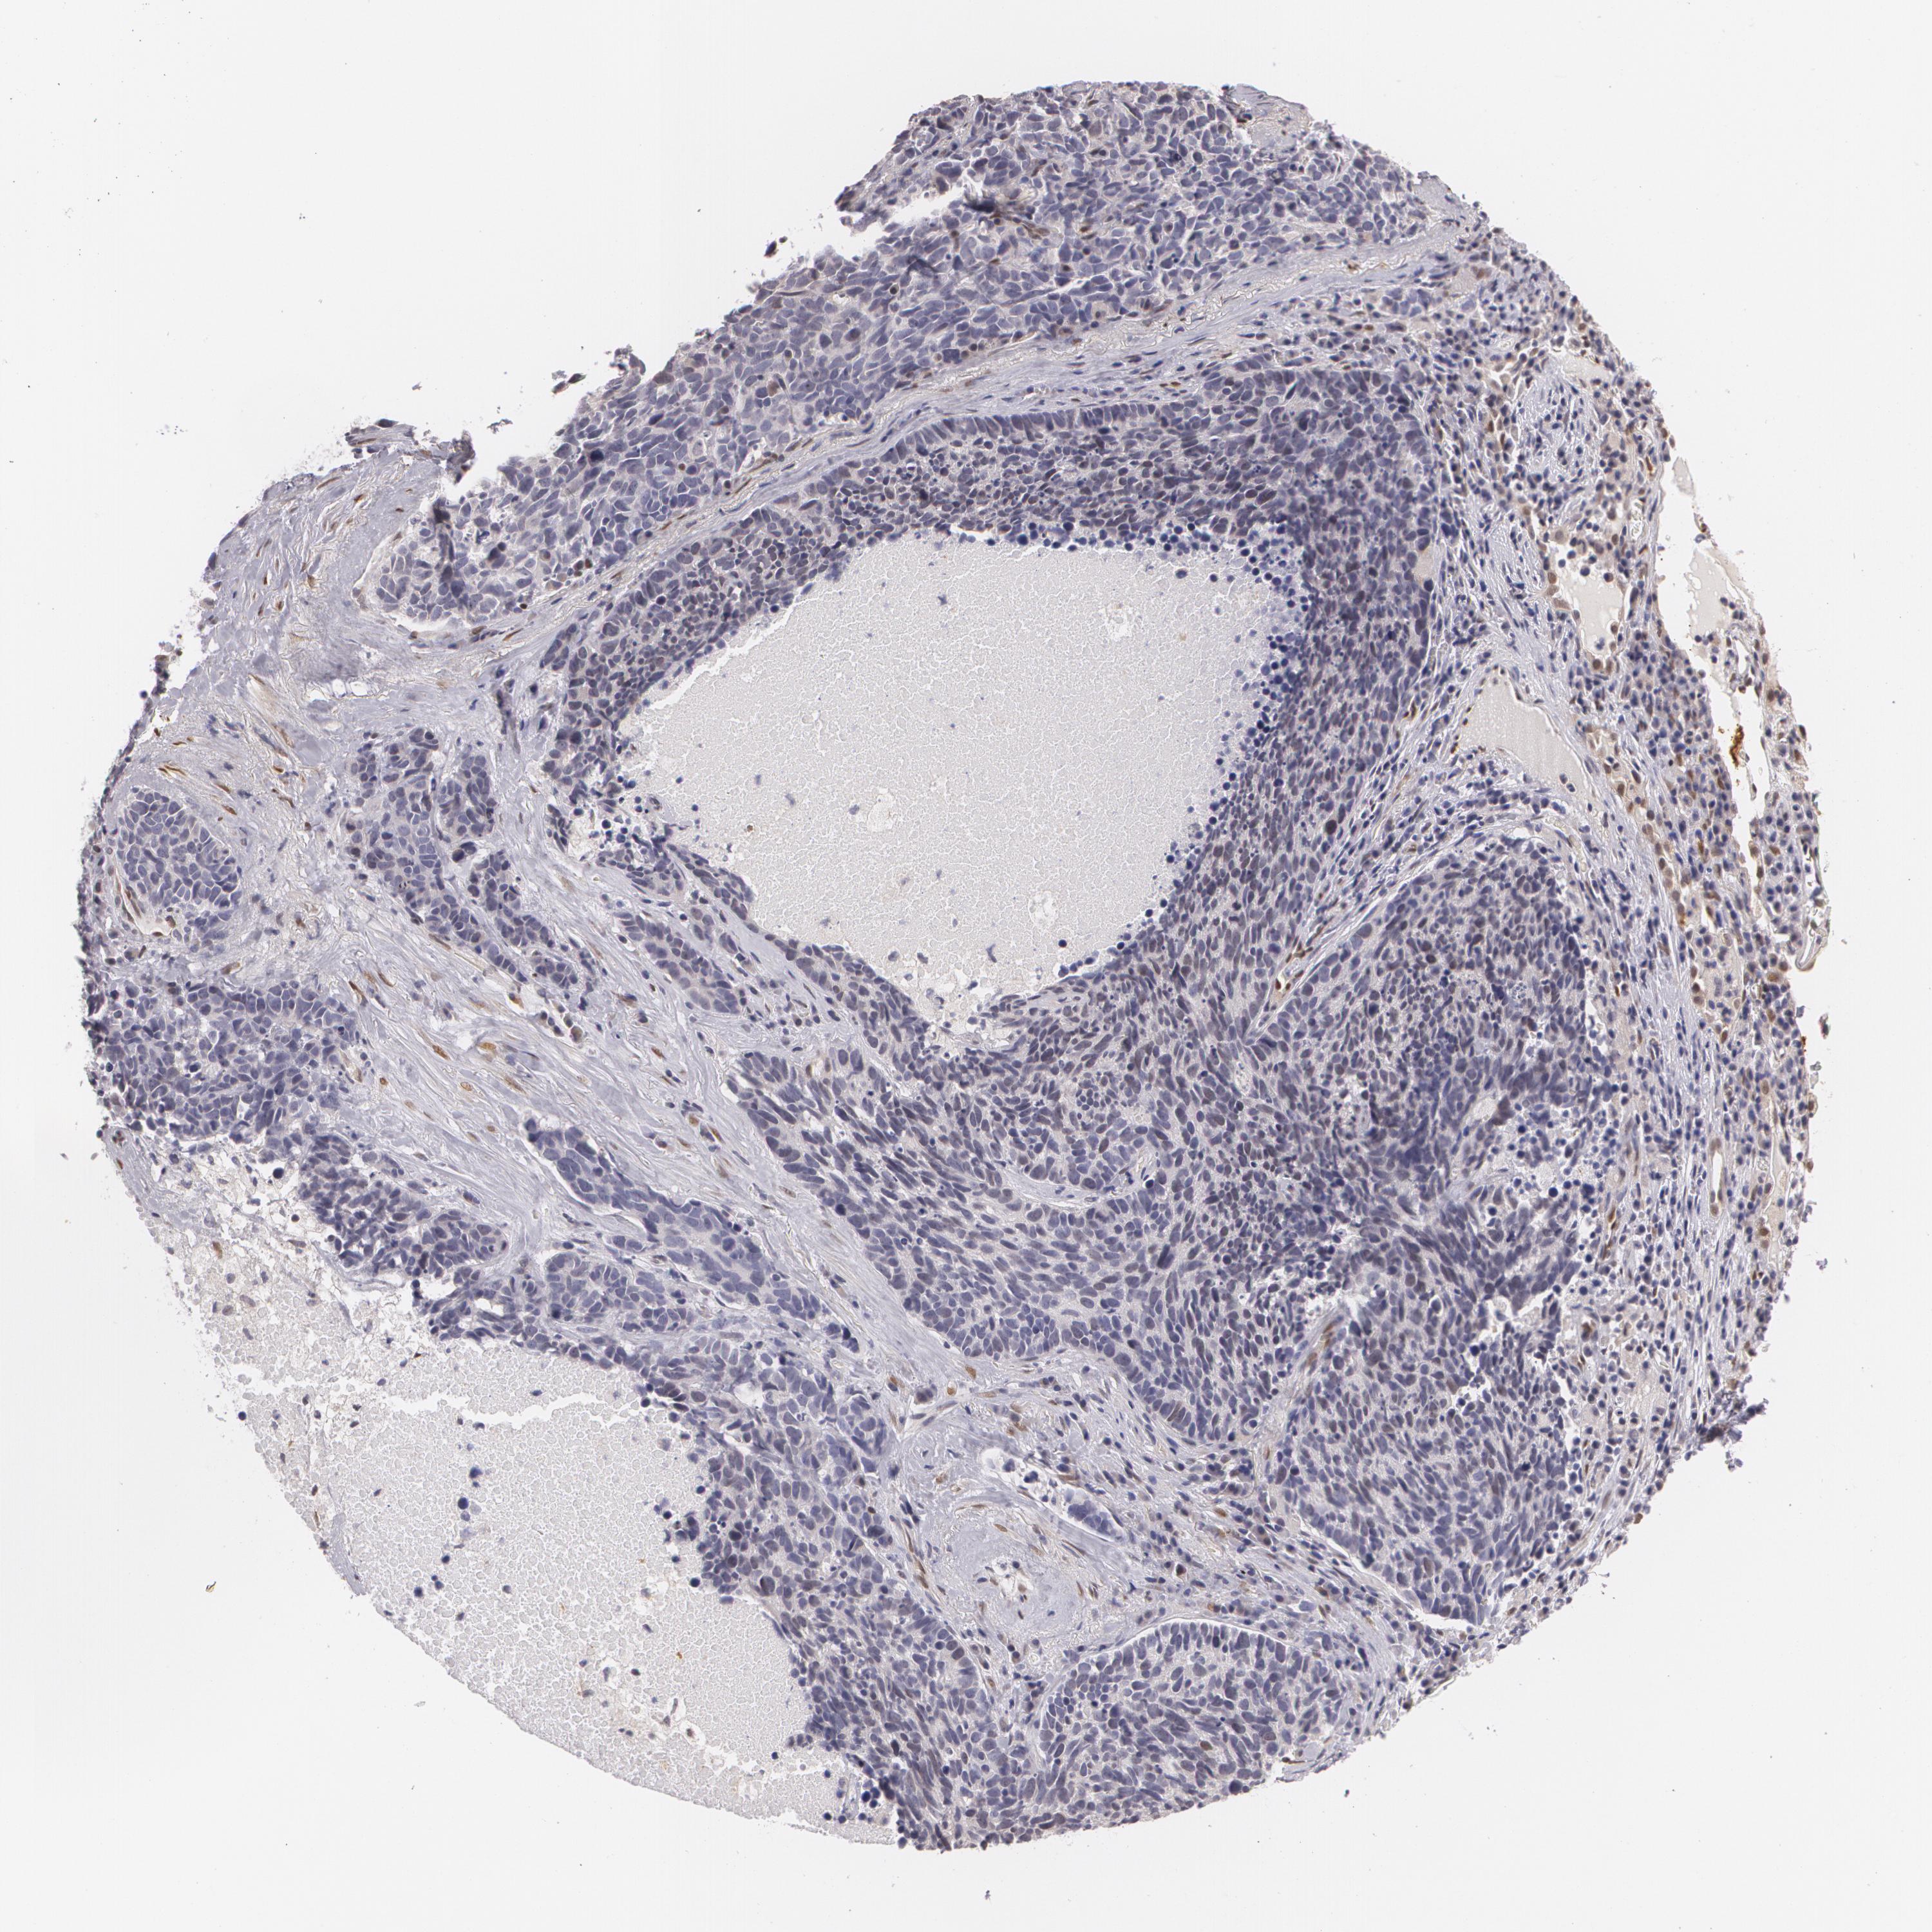

CANCER LUNG CANCER Show tissue menu

LUAD TCGA LUAD VALIDATION LUSC TCGA LUSC VALIDATION PROTEIN LUAD CPTAC PROTEIN LUSC CPTAC PROTEIN EXPRESSION

ANTIBODIES

AND

VALIDATION